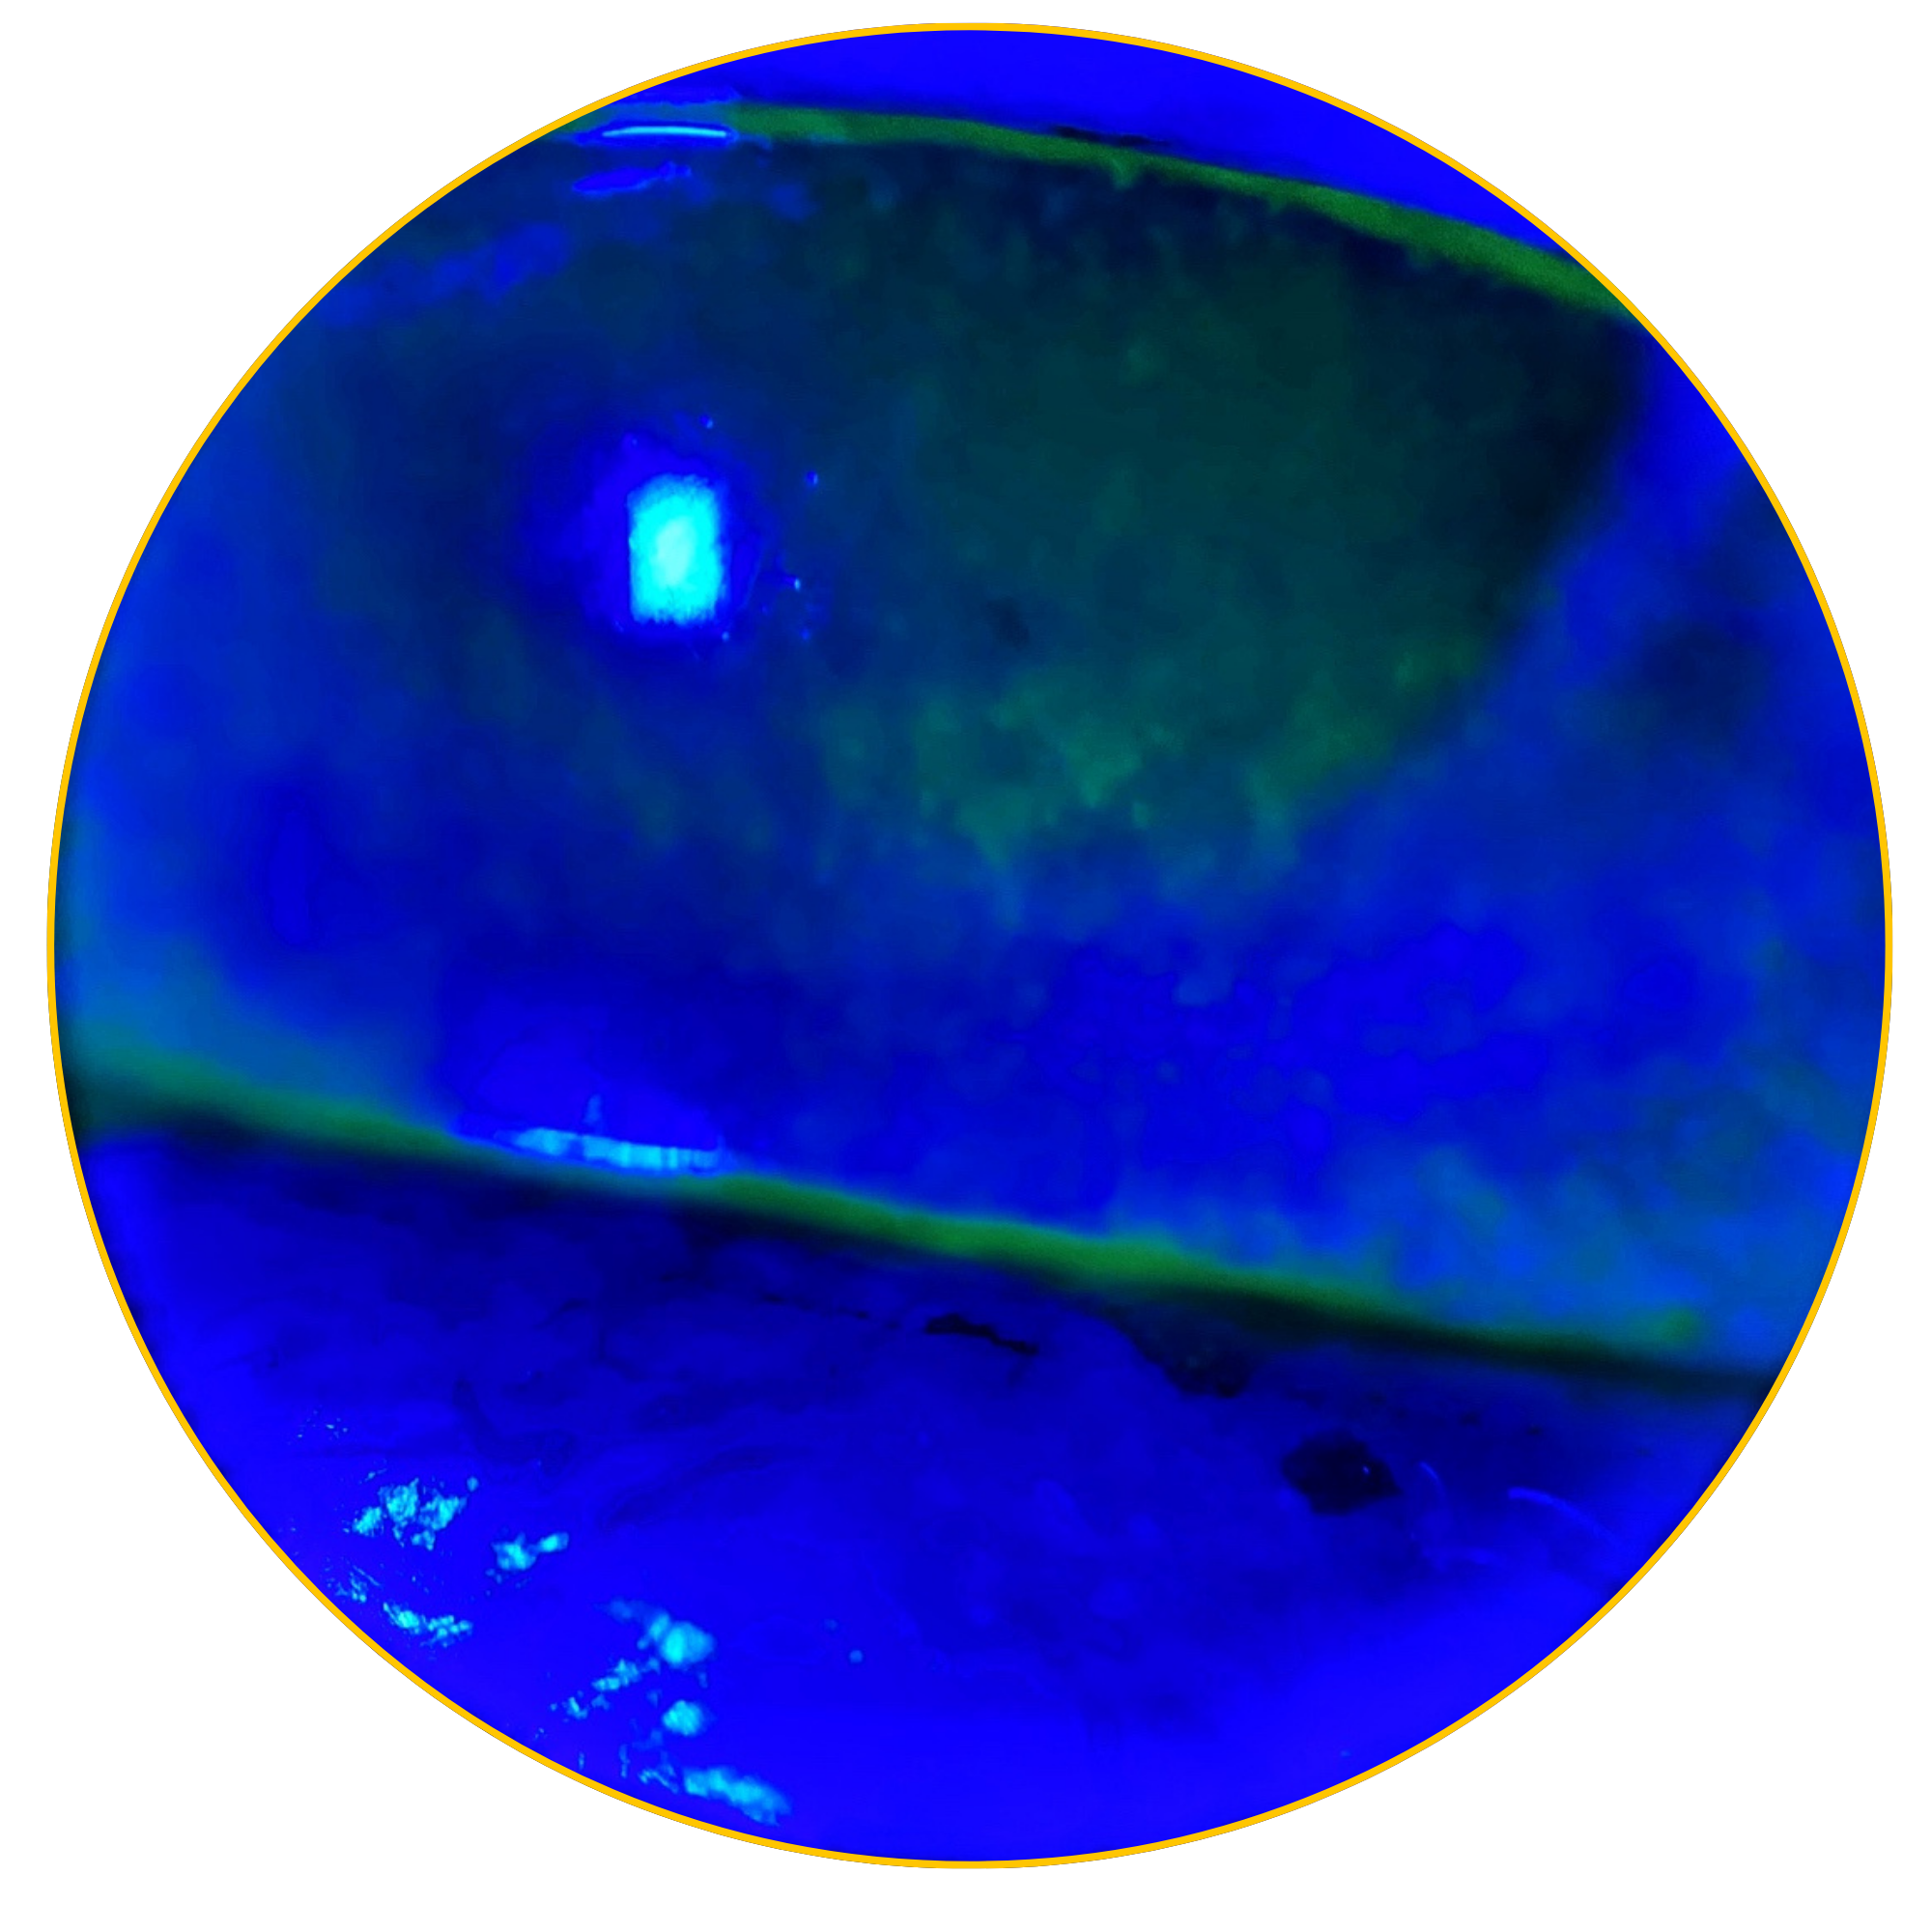

Some of the most challenging ocular surface cases can have overlapping causes. Since early-stage NK can look like Dry Eye,1 identifying it as a possibility may help bring the full picture into focus.

According to the Mackie classification, Stage 1 NK begins as early as Punctate Epithelial Keratitis (PEK).3 Lack of early detection can lead to corneal epithelial breakdown, impairment of healing, and development of corneal ulceration, melting, and perforation.4

Early detection & treatment are key to preventing further epithelial damage. Corneal sensitivity testing can help identify patients who may have underlying nerve damage and don’t respond to standard dry eye treatments.3 Detecting reduced sensitivity early can point to early stage Neurotrophic Keratitis and guide more targeted therapy to support healing and protect the cornea. Reduced corneal sensation affects nearly 10% of all eyes, and 30% of eyes with signs & symptoms of DED.1